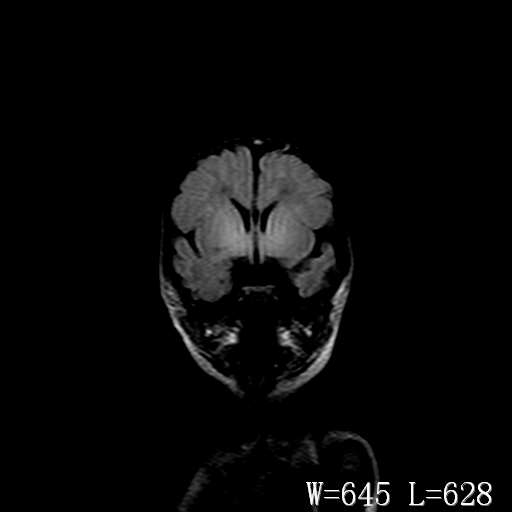

脑干形态欠规则,信号增高,不知怎么解释?

脑干背侧面t1高信号是,新生儿正常已经髓鞘化好的部位